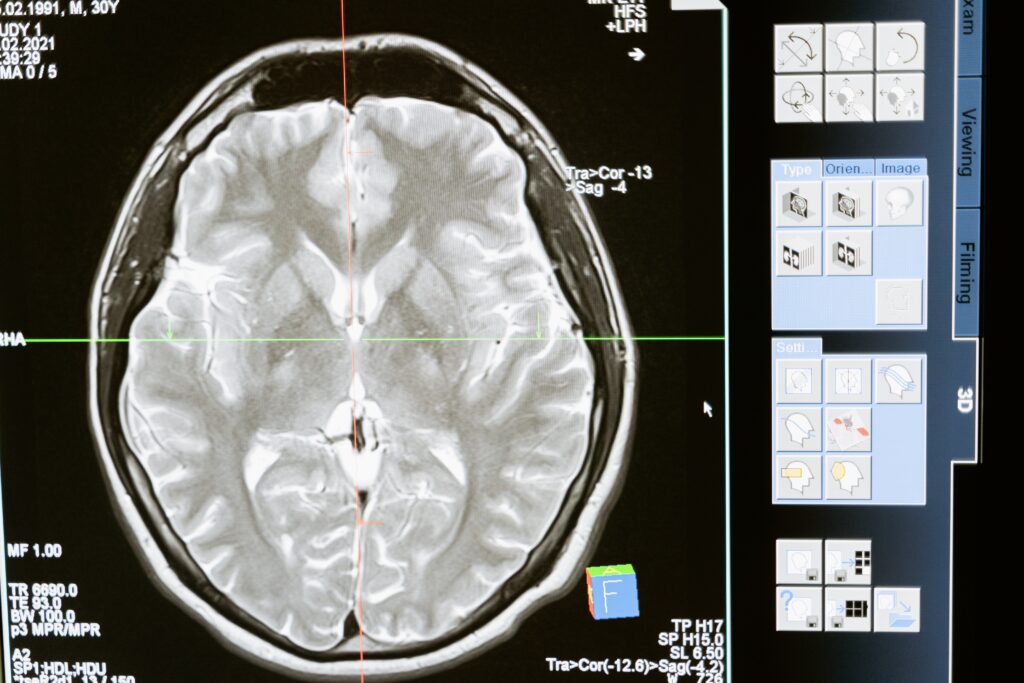

El grupo llevó a cabo una revisión de distintos estudios que empleaban la técnica conocida como resonancia magnética funcional (fMRI) para explorar la relación entre los efectos de los psicodélicos, la red neuronal por defecto (DMN) y la teoría de la mente (ToM).

La DMN, son un conjunto de regiones cerebrales que se activan cuando nuestra mente divaga o no está enfocada en una tarea específica. Durante estos momentos, reflexionamos sobre nosotros mismos, recordamos experiencias personales y proyectamos el futuro. Por otro lado, la ToM se refiere a nuestra capacidad de entender que otras personas tienen estados mentales diferentes a los nuestros, como creencias y emociones.

Sorprendentemente, los resultados revelaron que los psicodélicos interactúan con las áreas cerebrales relacionadas con la cognición social, específicamente el córtex cingulado anterior (ACC) y posterior (PCC). Estas regiones están vinculadas con la comprensión de emociones, o la atención, aspectos cruciales para entablar relaciones sociales, pero también en la perspectiva acerca de uno mismo y en las memorias autobiográficas. Por lo tanto, los resultados sugieren que los psicodélicos podrían inducir cambios significativos en la forma en la que nos relacionamos socialmente, al dar lugar a cambios en la perspectiva y los recuerdos de uno mismo.